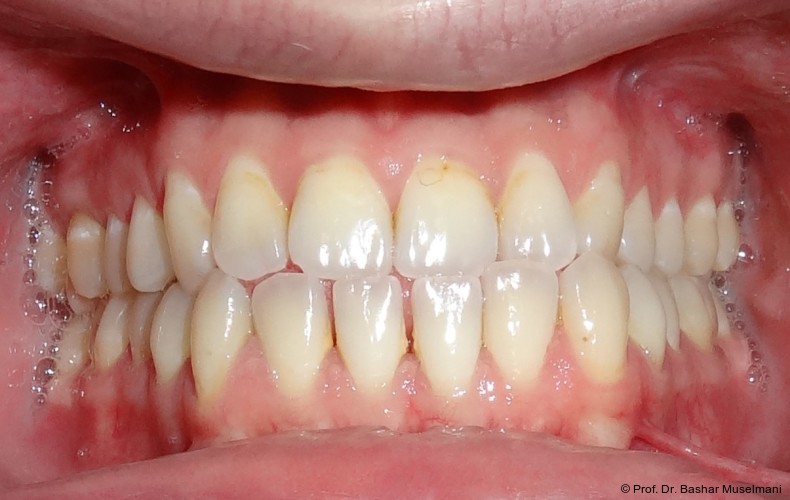

Abschlussbefund

Die Behandlung wurde mit 0.018 x 0.0275" TMA-Bögen abgeschlossen. Nach Entfernung der Multibracketapparatur zeigten sich:

• eine stabile Klasse I-Verzahnung

• ein normalisierter Overjet und Overbite

• deutliche Verbesserung der okklusalen Interdigitation

• ein ästhetisch harmonisiertes Profil

Die Behandlungsphase wird mit dem Einsetzen von TMA-Bögen im Ober- und Unterkiefer abgeschlossen (Abb. 10a–e). In den Abbildungen 11a bis c sind die extraoralen Aufnahmen nach Behandlungsabschluss und nach Entfernung der Brackets in beiden Kiefern dargestellt. Die Aufnahmen und die Kephalometrischen Analysen zeigen deutliche und rasche Veränderungen zwischen Behandlungsbeginn und -ende. Die Kephalometrischen Werten sind dabei von besonderer Bedeutung. Wie sich deutlich anhand des vergleiches der drei Behandlungsphase erkennen lässt.